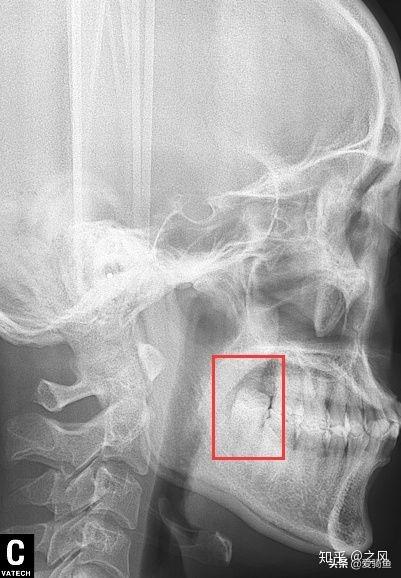

排隊(duì)等待叫號,進(jìn)去后張嘴檢查下,讓去拍片子,應(yīng)該就是我之前去的其他牙診所機(jī)構(gòu)的口掃,這里沒有給我電子照片,下面是以前拍的。

口掃

智齒